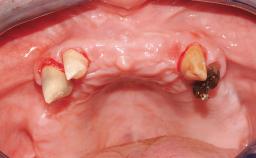

Immediate Loading of Four Implants in the Mandible and Final Restoration with a Full-Arch Metal Framework FDP

A fully edentulous 65-year-old woman was referred to our clinic for esthetic and functional dental rehabilitation. The patient presented with inadequate complete maxillary and mandibular prostheses, insufficient vertical dimension, and extensive tooth wear. The clinical examination and anamnesis showed no local or systemic contraindications, no signs or symptoms of bruxism, and an absence of smoking habits. The treatment proposed was implant placement in the mandibular interforaminal area and immediate loading with a fixed definitive prosthesis. A removable mucosa-supported complete prosthesis was indicated for the upper jaw, since its bone structure offered satisfactory retention and the financial condition of the patient disfavored a full-mouth implant-supported rehabilitation.

# of Implants 4

Defining Characteristics Fully edentulous lower jaw to be rehabilitated with an implant-borne fixed dental prosthesis